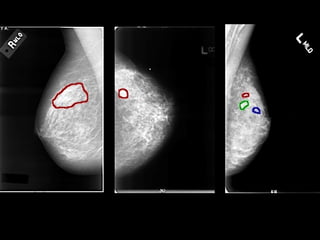

MAMOGRAFIA

RESSONÂNCIA MAGNÉTICA DA MAMA